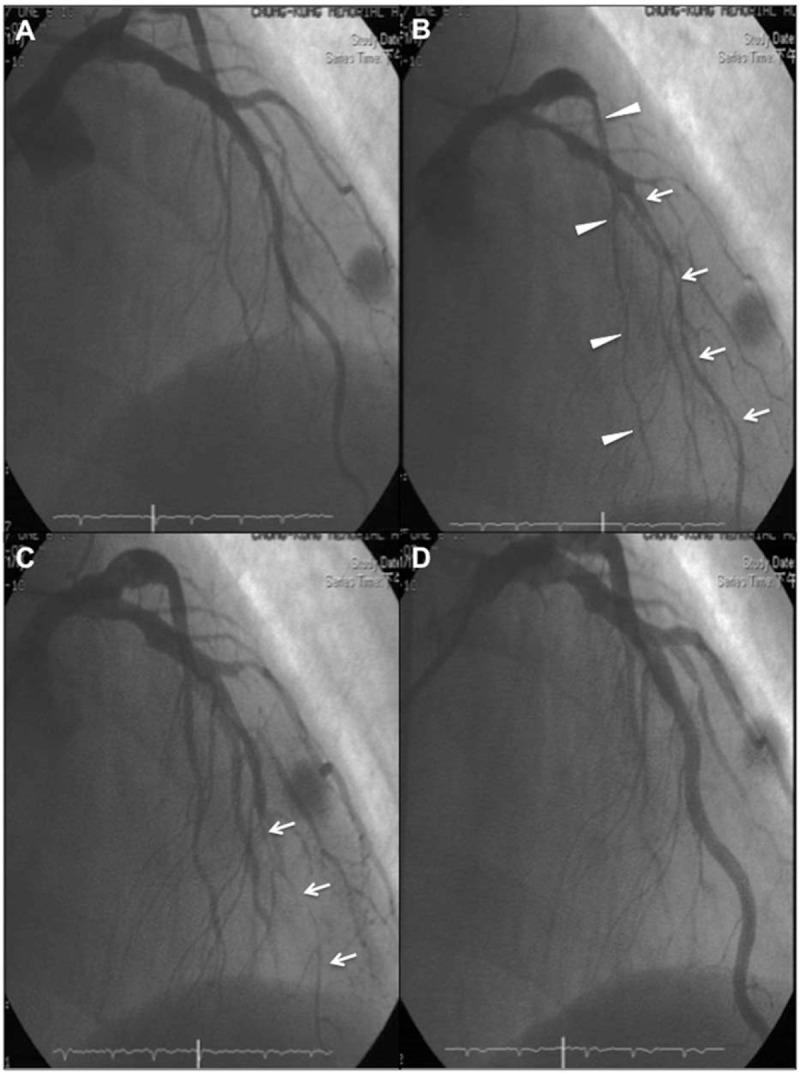

Vasospastic angina (VSA) was diagnosed based on electrocardiography and coronary angiography.

VSA can be associated with fluctuations in the amplitude of ST-segment elevation, indicating dynamic coronary vasospasm in different locations and extensions in patients with VSA.

根据心电图和冠状动脉造影诊断为变异性心绞痛(VSA)。

VSA可能与ST段抬高幅度的波动有关,提示VSA患者存在不同部位和范围的动态冠状动脉痉挛。